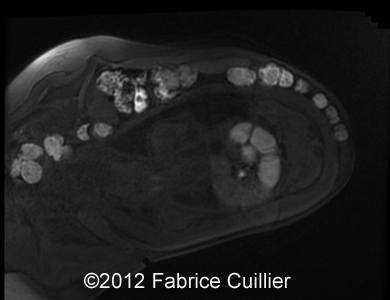

Image 8, 9: Abdominal fetal MRI  showed isolated intestinal dilatation with meconium inside.

9B

9A